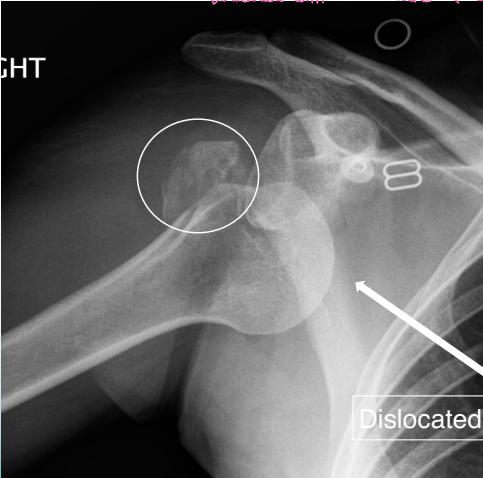

Posterior Shoulder Dislocation

Definition: The humeral head lies behind the glenoid

X-ray Findings:

- AP view:

- The humeral head is medially rotated → “Electric light bulb” sign

- The empty glenoid sign

- Posterior displacement

- Axillary & Scapular views are essential

- Rule-out fractures: neck, lesser tuberosity, glenoid